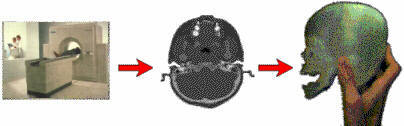

Bilgisayarlı tomografi veya MR verisine bağlı olarak model imalatı:

Eğer, CT ve MR cihazları ile hastanın istenilen organına ait 3D geometri verisini elde edilemiyor olsaydı, otoinşa teknolojisinin medikal uygulamarından söz etmek zor olurdu;

Solda: Gerekli medikal modelin inşası veya tasarımı için öncelikle hastanın istenilen uzvu mümkün olduğu kadar hassas bir şekilde (1mm) taranır

Ortada: Bazı özel yazılımlar ile CT veya MR verileri otoinşa cihazları ile imal edilecek stl formatına çevrilir.

Sağda: Bu veriler kullanılarak istenilen model inşa edilir.